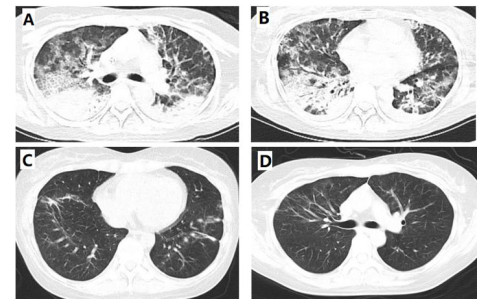

第一次收住院诊疗经过:完善常规生化提示低钾血症、高脂血症,超声心动图:微量心包积液,EF67%。肺通气功能正常。库欣综合征定性定位诊断方面,血总皮质醇(血F)(8AM) 69.6 μg/dL, ACTH(8AM) 664.0 pg/mL, 24 h尿游离皮质醇(24HUFC)2 723.2 μg/24 h,大剂量地塞米松抑制试验(见表 1); 标筛查:AFP 4.6 ng/mL, CA19-9 22.2 U/mL, CEA 3.0 ng/mL, CA125 38.4 U/mL, 细胞角蛋白19片段Cyfra211 6.0 ng/mL, CA242 19.0 U/mL, CA72-4 8.6 U/mL, CA15-3 12.9 U/mL, ProGRP 26.0 pg/mL, NSE 15.4 ng/mL。生长抑素受体显像:前纵隔结节,生长抑素受体高表达灶,考虑神经内分泌肿瘤可能性大;双侧肾上腺增生。(图 1C);垂体平扫+动态增强MRI:垂体后叶短T1信号存在垂体左翼强化减低区,考虑微腺瘤。胸增强CT:前纵隔占位,结合病史,不除外异位ACTH瘤(图 1A);TB细胞亚群11项: %memory T4 78.1%, B% 17.9%, T4% 17.6%, T8% 42.1%, RAT4% 21.9%, NaT4% 21.7%, 28T8% 32.1%, DRT 8% 76.2%, 38T8% 83.0%, T4/T8 0.42%, 垂体前叶功能,甲功1:TSH 0.077 μIU/mL, FT4 1.73 ng/dl, FT3 2.17 pg/mL, GH < 0.05 ng/mL, IGF1 132 ng/mL。FSH 2.13 IU/L, LH 0.26 IU/L, E2(Ⅱ) < 15 pg/mL, T 1.96 ng/mL, PRL 6.9 ng/mL, P 5.31 ng/mL。MEN筛查,GASTRIN 260 pg/m,ProGRP 23.9 pg/mL。降钙素(CT) < 1.5 pg/mL,钙素原PCT 0.23 ng/mL, CK 33 U/L。IPSS+DDAVP兴奋试验示基线时中枢和外周ACTH无梯度(见表 2),结合大剂量地塞米松抑制实验不被抑制,支持异位ACTH综合征,考虑胸腺占位为责任病灶可能。治疗方面,入院后予口服及静脉补钾、螺内酯纠正低钾血症,监测血糖,餐后2 h血糖高,给予胰岛素及口服降糖药后血糖基本达标。患者前纵隔结节考虑为异位ACTH瘤可能大,2020-08-26行VATS胸腺及肿瘤切除术,术后恢复良好,激素替代方案由围术期静脉应用琥珀酸氢化可的松逐渐过渡为醋酸氢化可的松片早40 mg,晚20 mg替代治疗后出院(图 3主要指标趋势及用药情况)。2020-08-31无明显诱因出现发热,体温最高达39℃,当地诊所静点“头孢类抗生素”、口服布洛芬治疗2 d,仍间断发热,并出现站立后头晕,当时血压76/40 mmHg,就诊当地医院,查血常规:WBC 6.01×109/L, NEUT% 85.2%, LYM% 13%; CRP 194.74 mg/L; CMV DNA阳性;胸部CT提示双肺弥漫渗出,考虑“重症肺炎I型呼吸衰竭”于当地重症监护室予以“无创呼吸机辅助呼吸,哌拉西林他唑巴坦、奥司他韦、伏立康唑抗感染,丙种球蛋白免疫支持”。治疗效果欠佳,胸闷、憋气逐渐加重,伴咳少许白色黏痰。2020-09-03就诊本院,考虑重症肺炎收入急诊重症监护病房,第2次收住院诊疗经过:呼吸方面:复查胸CT提示:双肺弥漫炎性改变,双侧胸腔积液并左下肺轻度膨胀不全(图 2A 、B)。予高流量氧疗支持,完善肺泡灌洗液: PCP DNA阳性(+),CMV(+),结合病史、症状、体征及辅助检查证据,考虑肺孢子菌肺炎、巨细胞病毒肺炎、混合细菌感染,头孢他啶1 g/8 h、莫西沙星0.4 g/d、TMP/SMX 3片3次/d,更昔洛韦0.25 g/8 h,呼吸困难逐渐改善,复查CT病灶明显吸收(图 2C 、D)。内分泌方面:考虑EA导致CS术后,激素替代治疗中合并机会性感染,调整治疗:停用口服,给予琥珀酸氢化可的松50 mg/6 h。口服降糖药控制类固醇糖尿病,口服碳酸钙片治疗骨质疏松。原发病方面:结合病理胸腺病灶考虑内分泌来源类癌,恶性程度低,无需放化疗。2020-09-30出院时患者无发热、头晕、纳差、恶心、呕吐、电解质紊乱、低血糖等肾上腺皮质功能不全表现,氢化可的松早40 mg-午20 mg逐渐减量(图 3主要指标趋势及用药情况),激素替代期间TMP/SMX 2片/d预防感染,门诊随诊。

| 图 2 9-4 A、B双肺间质弥漫性渗出伴炎性改变,双下肺实变影9-16 C、D治疗后复查双肺炎性改变较前明显改善 |